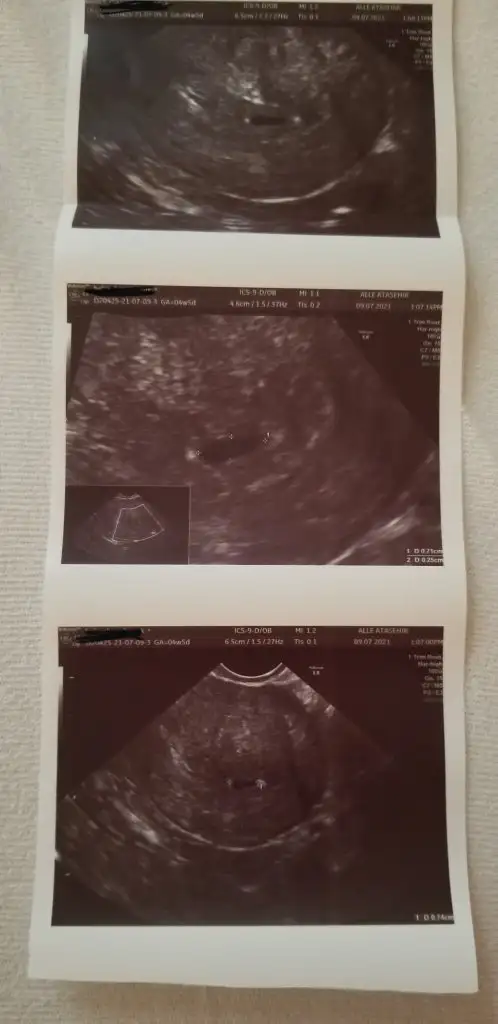

Selam kızlar benim kese yuvarlak değil. doktor yapısını çok beğendi.içime kurt düştü.düşükten sonra ikna olamıyorum. bir yerde okudum.kese yuvarlamaz kız yardıysa erkek yazıyor. düzensiz değil değilmi şeklii.bi de kese 7 mm mi oluyor

• 20210710_111056.webp

20210710_111056.webp

18,7 KB · Görüntüleme: 71

Canım bu kese olayını okumuştum bnde burda keseye göre cinsiyet tahmini topiginde .orda da böyle keseker vardı bı bak istersen . Kese böyle olunca erkek diyolardi . Mesela Bnm kızımın ilk kese ultrasonuna baktım onun ki yuvarlakti .